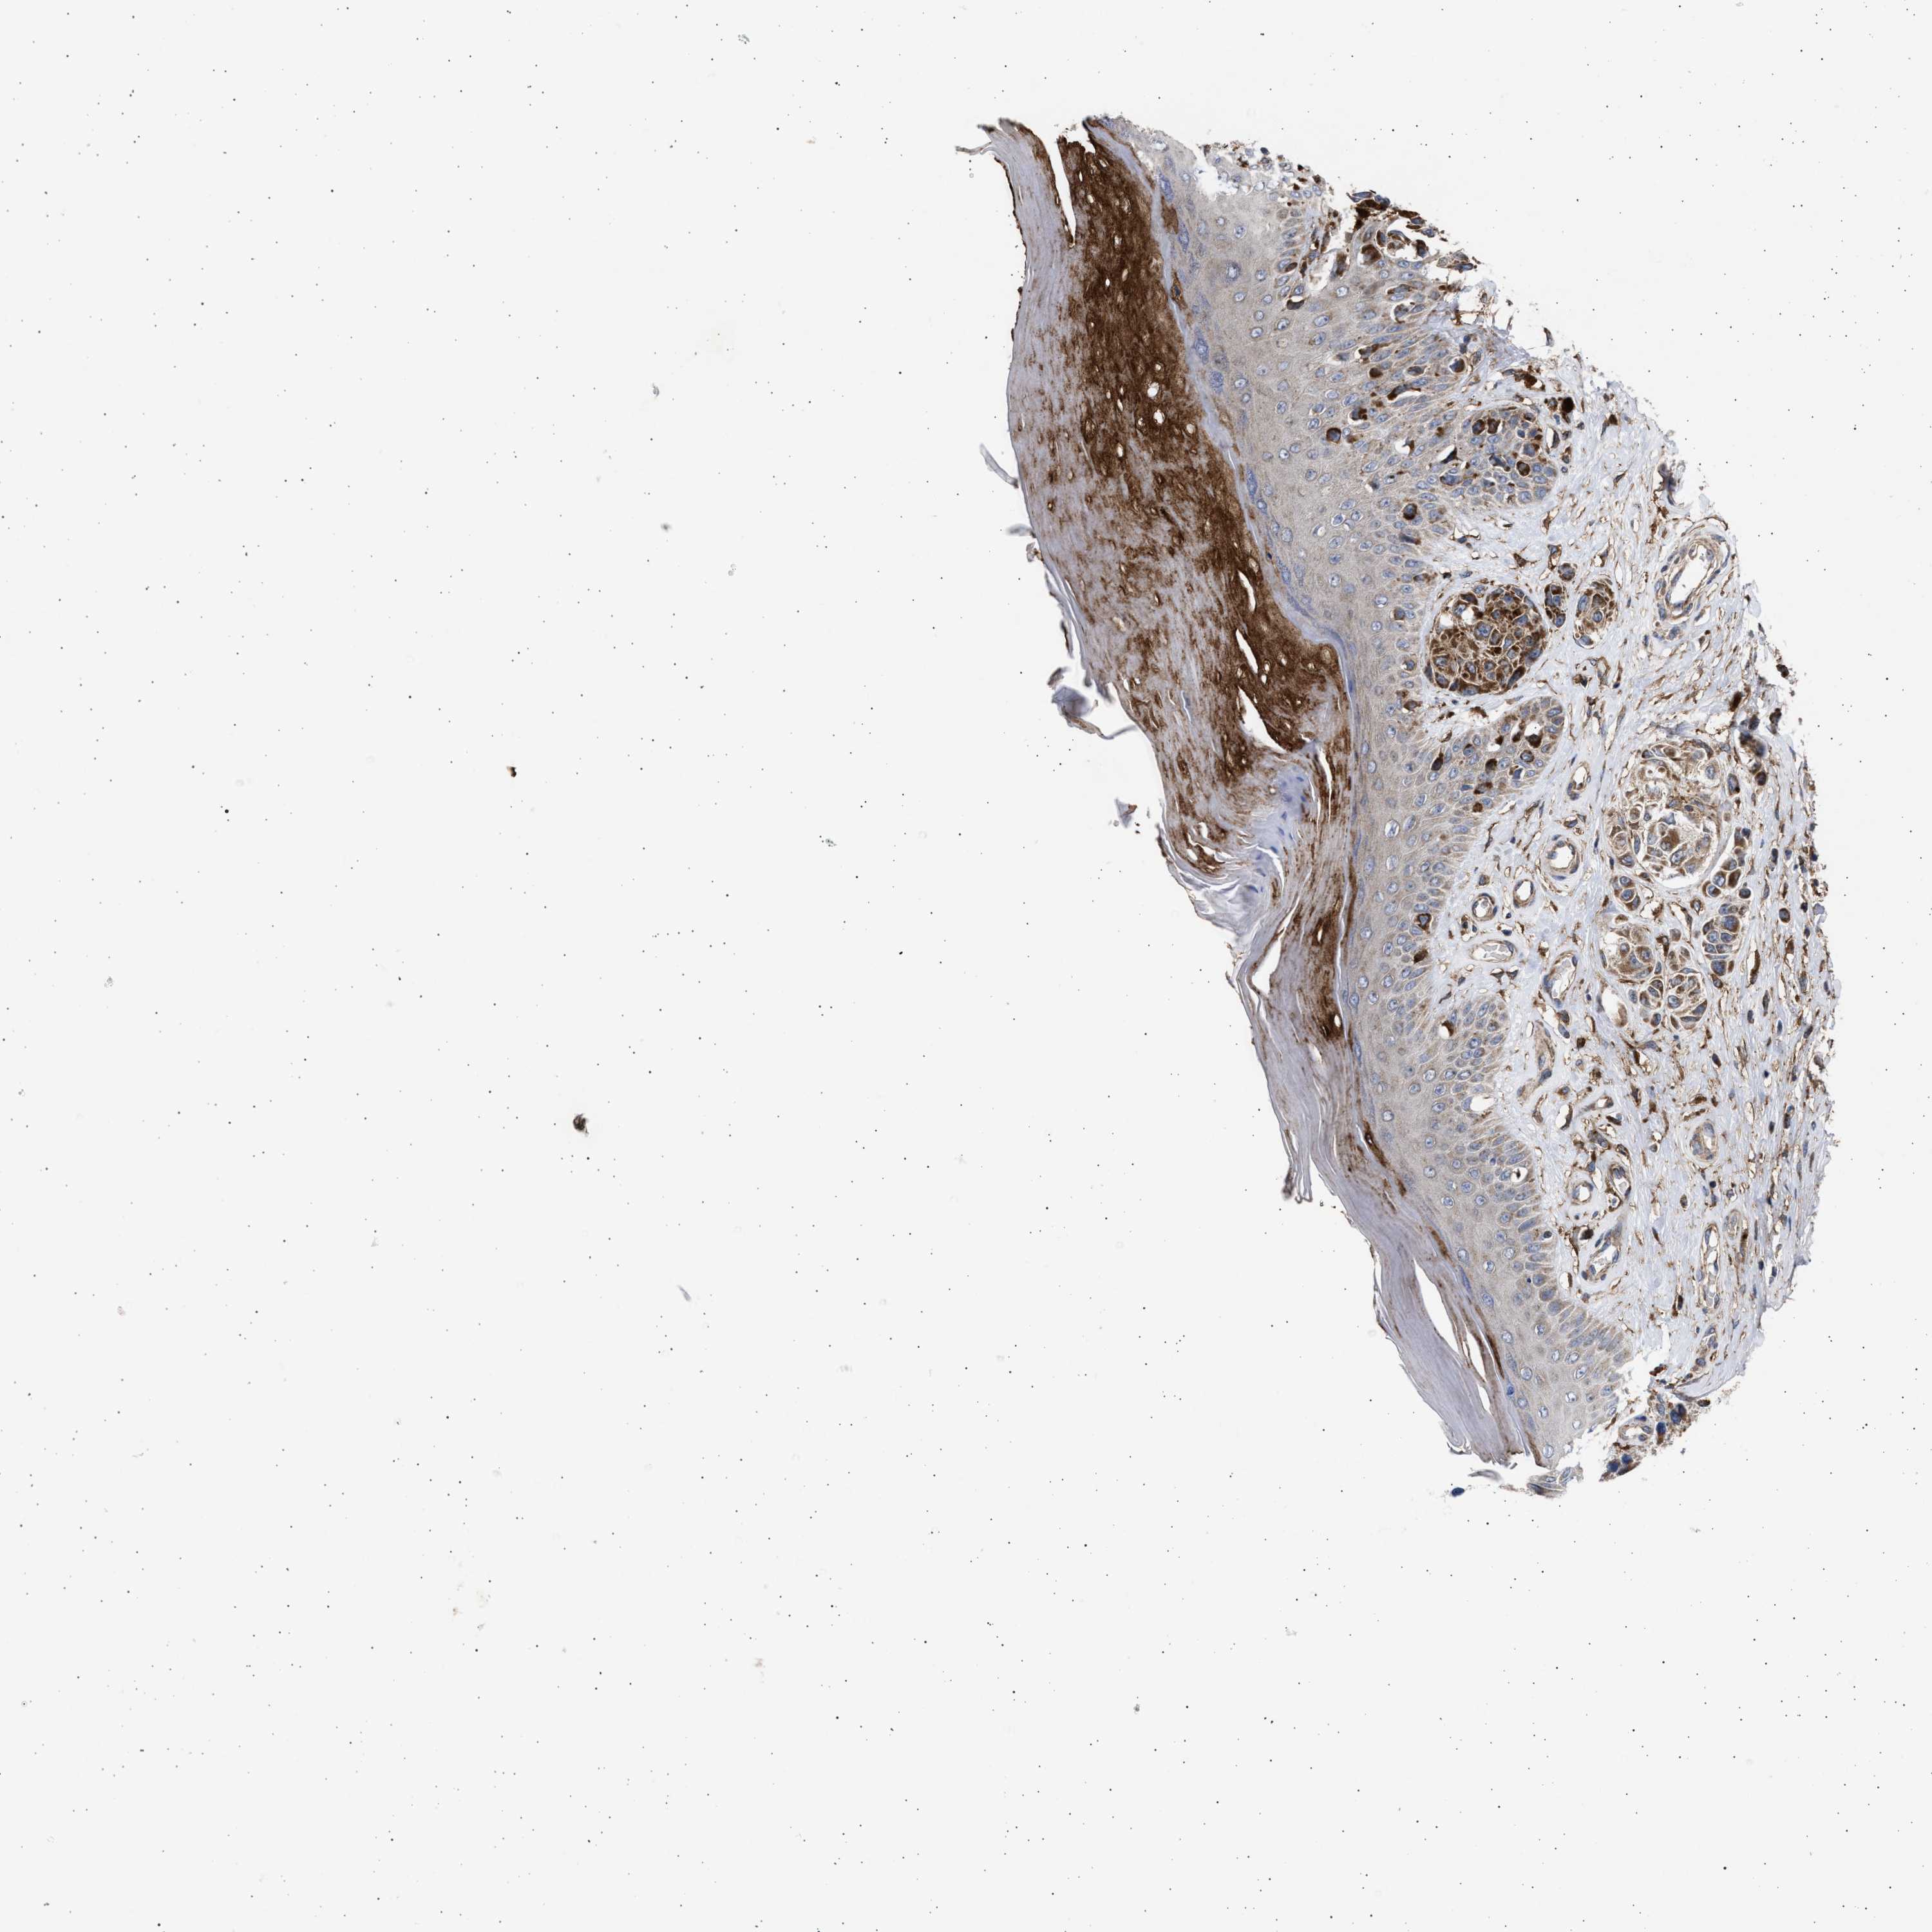

MELANOMA - Protein expressioni

A mouse-over function shows sample information and annotation data. Click on an image to view it in a full screen mode. Samples can be filtered based on level of antibody staining by selecting one or several of the following categories: high, medium, low and not detected. The assay and annotation is described here.

Note that samples used for immunohistochemistry by the Human Protein Atlas do not correspond to samples in the TCGA dataset.

Antibody stainingi

Antibody staining in the annotated cell types in the current human tissue is reported as not detected, low, medium, or high, based on conventional immunohistochemistry profiling in selected tissues. This score is based on the combination of the staining intensity and fraction of stained cells.

Each image is clickable and will lead to virtual microscopy that enables deeper exploration of all samples and also displays staining intensity scores, fraction scores and subcellular localization as well as patient and tissue information for each sample.

Antibody HPA023010

Antibody HPA052380

Staining

High

Medium

Low

Not detected

Intensity

Strong

Moderate

Weak

Negative

Quantity

>75%

75%-25%

<25%

None

Location

Nuclear

Cytoplasmic/membranous

Cytoplasmic/membranous,nuclear

Malignant melanoma, NOS

Malignant melanoma, Metastatic site